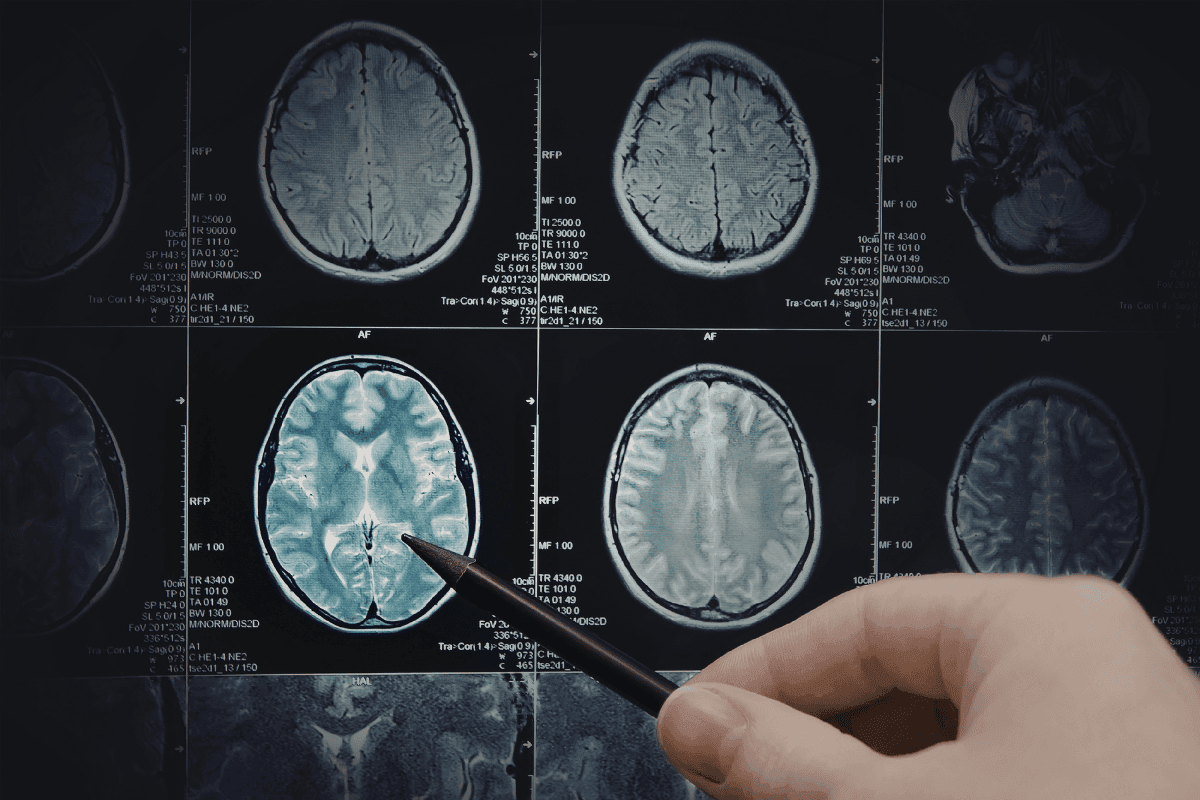

Neurología

Evaluamos y tratamos enfermedades del sistema nervioso con un enfoque integral orientado al diagnóstico oportuno y al seguimiento de cada paciente.

La neurología es la especialidad médica dedicada al diagnóstico, tratamiento y seguimiento de enfermedades del cerebro, la médula espinal, los nervios y los músculos. La American Academy of Neurology explica que los neurólogos tratan enfermedades del sistema nervioso como Alzheimer, accidente cerebrovascular, conmoción cerebral, epilepsia, Parkinson, esclerosis múltiple, cefaleas y migraña.

En CEMédica, el área de Neurología contempla evaluación y manejo de neurología vascular, paciente grave, enfermedades neuroinflamatorias, demencias, epilepsias, migraña, enfermedades extrapiramidales y neuromusculares. Esta especialidad es importante cuando existen síntomas como dolores de cabeza persistentes, alteraciones de memoria, crisis convulsivas, mareos, temblores, debilidad o cambios en la movilidad.